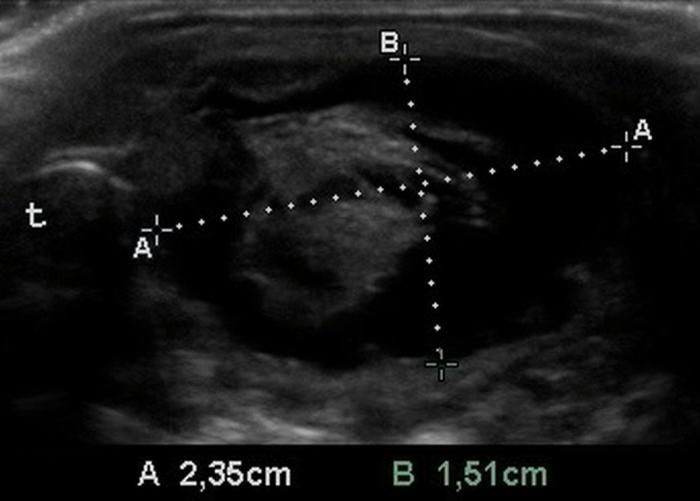

El uso de estructuras vasculares adyacentes como referencias anatómicas ha sido una estrategia útil en ecografía veterinaria para estandarizar las mediciones de órganos pequeños como la glándula tiroides. En este contexto, Bandula Kumara et al. (2019) propusieron la medición de la relación entre el diámetro tiroideo (TD) y el diámetro de la arteria carótida común (CCA) como una forma práctica de evaluar el tamaño de la glándula en perros clínicamente normales (Figura 5A-B).

Los autores realizaron un estudio en el que midieron el diámetro anteroposterior de los lóbulos tiroideos y el diámetro externo de la CCA en cortes transversales obtenidos a nivel del cuello medio. Encontraron que esta relación se mantiene relativamente constante entre razas y tamaños corporales, sugiriendo que puede ser utilizada como parámetro de referencia ecográfica. Específicamente, en perros adultos sanos, la relación TD/CCA fue de 1.74 ± 0.40 (rango 1.11–2.43)6. Si los valores se encuentran por debajo del rango normal pueden ser considerados potencialmente indicativos de hipoplasia tiroidea o atrofia glandular.

Una ventaja de esta relación es que la arteria carótida común es fácilmente identificable ecográficamente, presenta un diámetro estable y poco variable en condiciones fisiológicas, y se ubica en estrecha proximidad con la glándula tiroides. Esto la convierte en una excelente estructura de referencia para normalizar mediciones entre individuos de diferente tamaño corporal, permitiendo evaluaciones objetivas en poblaciones mixtas de perros de compañía.